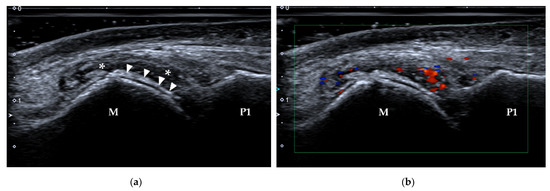

4.1.3. Stress Fracture

| Stress fracture | 2nd and 3rd metatarsals | periosteal lifting or cortical disruption, hypoechoic hematoma above the cortical bone |